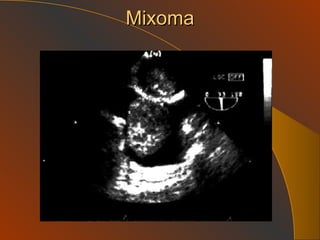

Mixoma

HTP Secundaria :a. Enfermedades Cardiacas Congenitas: CIA, CIV, Cor TriA, PDA, Ventana Ao P Adquiridas: causantes de incremento de P venas pulm. Enf Mitral severa, Enf. V.Ao. Severa, Disfuncion VI, amiloidosis HTP etiologia Cardiopatías y Valvulopatías izq:  Presión Auricula izq  Presión Venas Pulmonares  Presión Arteria Pulmonar